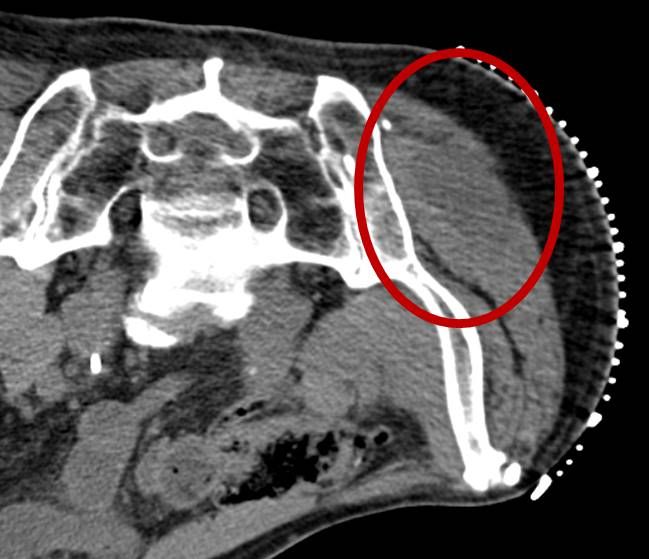

Eine Vielzahl von Krankheitsdiagnosen basiert auf der mikroskopischen bzw. histologischen Untersuchung körpereigener Gewebe, die auf möglichst schonende Weise entnommen und anschließend im Labor bzw. unter dem Mikroskop untersucht werden. Bei der perkutanen Biopsie punktiert der Arzt mit einer dünnen Nadel durch die Haut hindurch ('perkutan') das Zielorgan und entnimmt so eine kleine Menge Flüssigkeit oder ein kleines Gewebestück. Der Eingriff kann im Regelfall in örtlicher Betäubung durchgeführt werden. Um das Zielgewebe möglichst sicher zu treffen, führen wir die meisten Biopsien unter CT-Steuerung, alternativ unter sonographischer Steuerung, durch. Ist die Zielläsion nicht sicher im CT oder im Ultraschall zu erkennen, führen wir die Biopsie mit speziellen Biopsie-Systemen im Einzelfall auch unter MRT-Kontrolle durch.